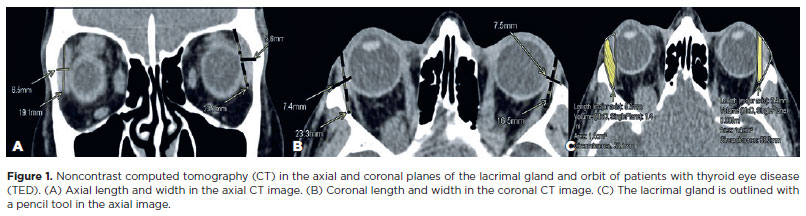

CT scan images were reviewed on a picture archiving and communication system workstation using a commercial AGFA Enterprise Imaging workstation. The CT scan data were acquired using the Discovery 750 HD 64 Slice scanner (GE Healthcare, Milwaukee, WI, USA), with a scanning protocol of 0.6-mm axial, nonoverlapping contiguous sections for the orbits. This was achieved by tilting the patient´s head parallel to the Frankfurt plane. Quantitative measurements of the LG were performed by a senior neuroradiologist (SE). Each orbit of the patient was considered as one unit for calculation. Two measurements of both LG parameters were performed on the selected images using a previously described method(11,12). The axial and coronal soft tissue series were the places where the LG appeared the largest to document dimensions in millimeters. The axial length (AL) of the LG was defined as the distance between the most anterior tip to the most posterior tip of the LG. Axial width (AW) was measured from the lateral to the medial edge at its widest point perpendicular to the length line on the axial images (Figure 1A). Coronal length was measured from the superior to the inferior tip of the LG. Coronal width (CW) was measured from the lateral edge to the medial edge at its widest point perpendicular to the length line on the coronal images (Figure 1B). The LG volume was obtained using a manual tracer approach following the delineation of the LG borders in each section on the axial and coronal images; the results were reported in cubic centimeters (Figure 1C).